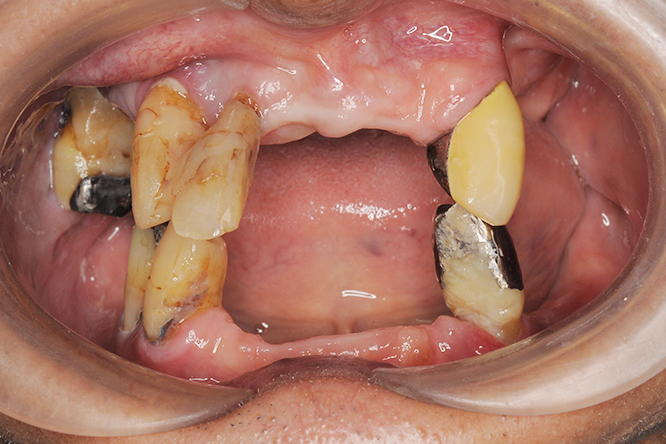

こちらの写真は、上下の顎をオールオン4で治療した際のビフォーアフターを示しています。

歯や歯茎が自然な色合いを持っていることにご注目ください。